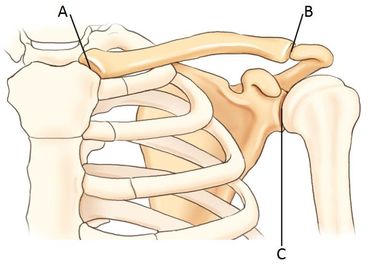

A. sternoclavicular joint (SC) B. acromioclavicular joint (AC) C. scapulohumeral joint (glenoid cavity)